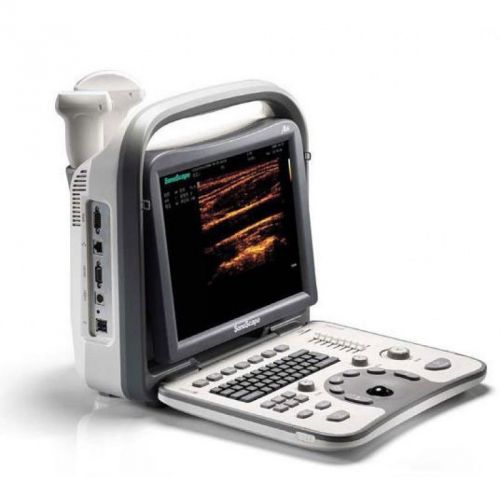

NEW SonoScape A6 + 1 standard Probe